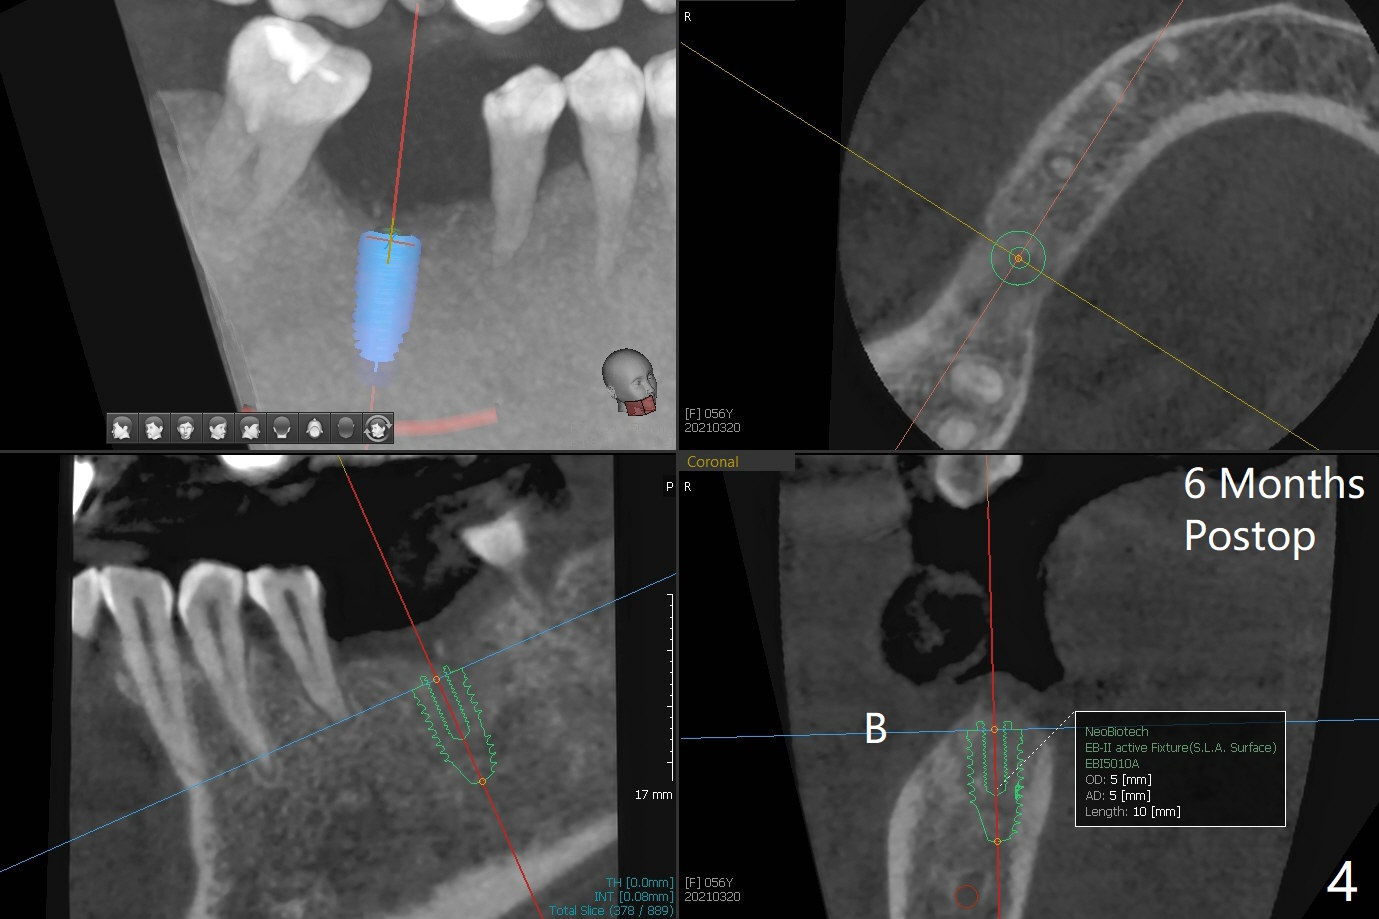

即刻植牙对害怕病人有一个好处,快速结束治疗,安慰病人可是一个麻烦事。即刻种植也可以发生于拔除失败植体之后。今天拔除的失败植牙不知厂家,基台螺丝刀对不上号,所以当植体取出时,病人和我都筋疲力尽,临时决定不做即刻种植。但是出现一个问题,事先准备粘性骨块不够,形成粘性骨块后的上清液不再形成粘性骨块,虽然仍然含有血小板,这样松散的骨粉如果放在牙槽窝上端比较容易丢失。我们解决方法是先把不粘稠的骨粉放在底层(图一:N),把粘性骨块放在上面(S),之后放置PRF膜以及不可吸收膜,使用PTFE缝线和牙周敷料。术后疼痛严重,创伤大。术后4个月牙槽嵴中央塌陷(图二)。不过还能植入5x10毫米植体(图三,四)。Return to Armaments No Deviation Xin Wei, DDS, PhD, MS 1st edition 09/15/2020, last revision 04/06/2021